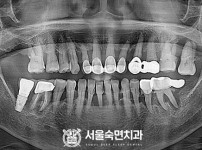

임플란트-전후사진4